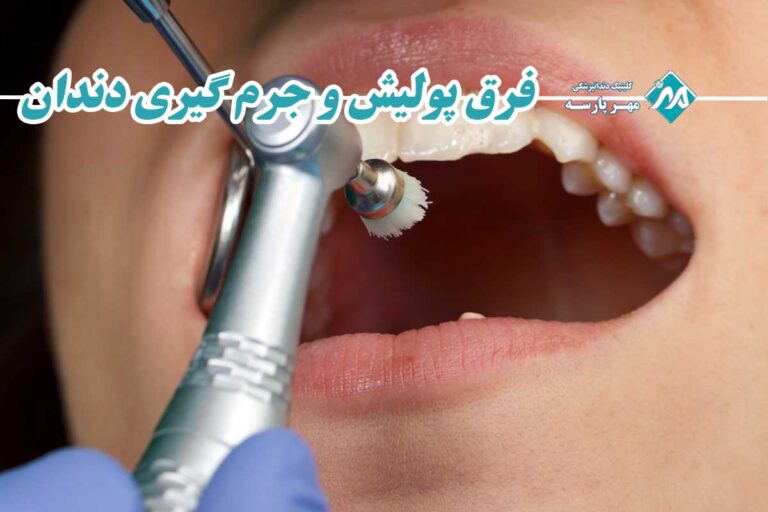

آیا تا به حال حس کردهاید که حتی بعد از بهترین و دقیقترین مسواک زدنها، هنوز یک لایه زبر و کدر روی دندانهایتان باقی مانده